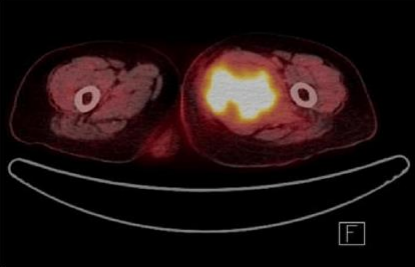

Magnetic resonance imaging (MRI) revealed a 4.7x7.2x9 cm irregular soft tissue mass in the left medial proximal thigh involving the adductor magnus muscle. The mass demonstrated intermediate and heterogeneous T2 signal intensity with an irregular peripheral T2 dark signal rim and intermediate T1 signal intensity. Additionally, the MRI showed extensive surrounding muscle and subcutaneous edema with a branch of the deep femoral artery coursing through the mass. Gadolinium-enhanced images revealed multilocular cystic areas surrounded by intense heterogeneous enhancement of the solid components. The mass demonstrated features concerning for malignancy [Figure 1, 2, 3, 4]. A fluorodeoxyglucose (F-18 FDG) PET scan demonstrated mildly hypermetabolic lymph nodes in the left inguinal region (suspected reactive) and a few small inflammatory nodules without FDG uptake in both lungs, but no evidence of distant metastasis [Figure 5].

FI GURE 5: FDG-PET Hypermetabolic lesion in adductor compartment of thigh